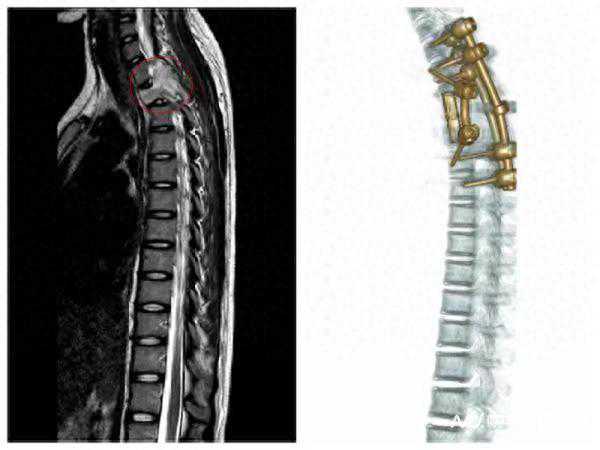

15岁女孩颈部酸痛竟致瘫痪,原来是胸椎长肿瘤